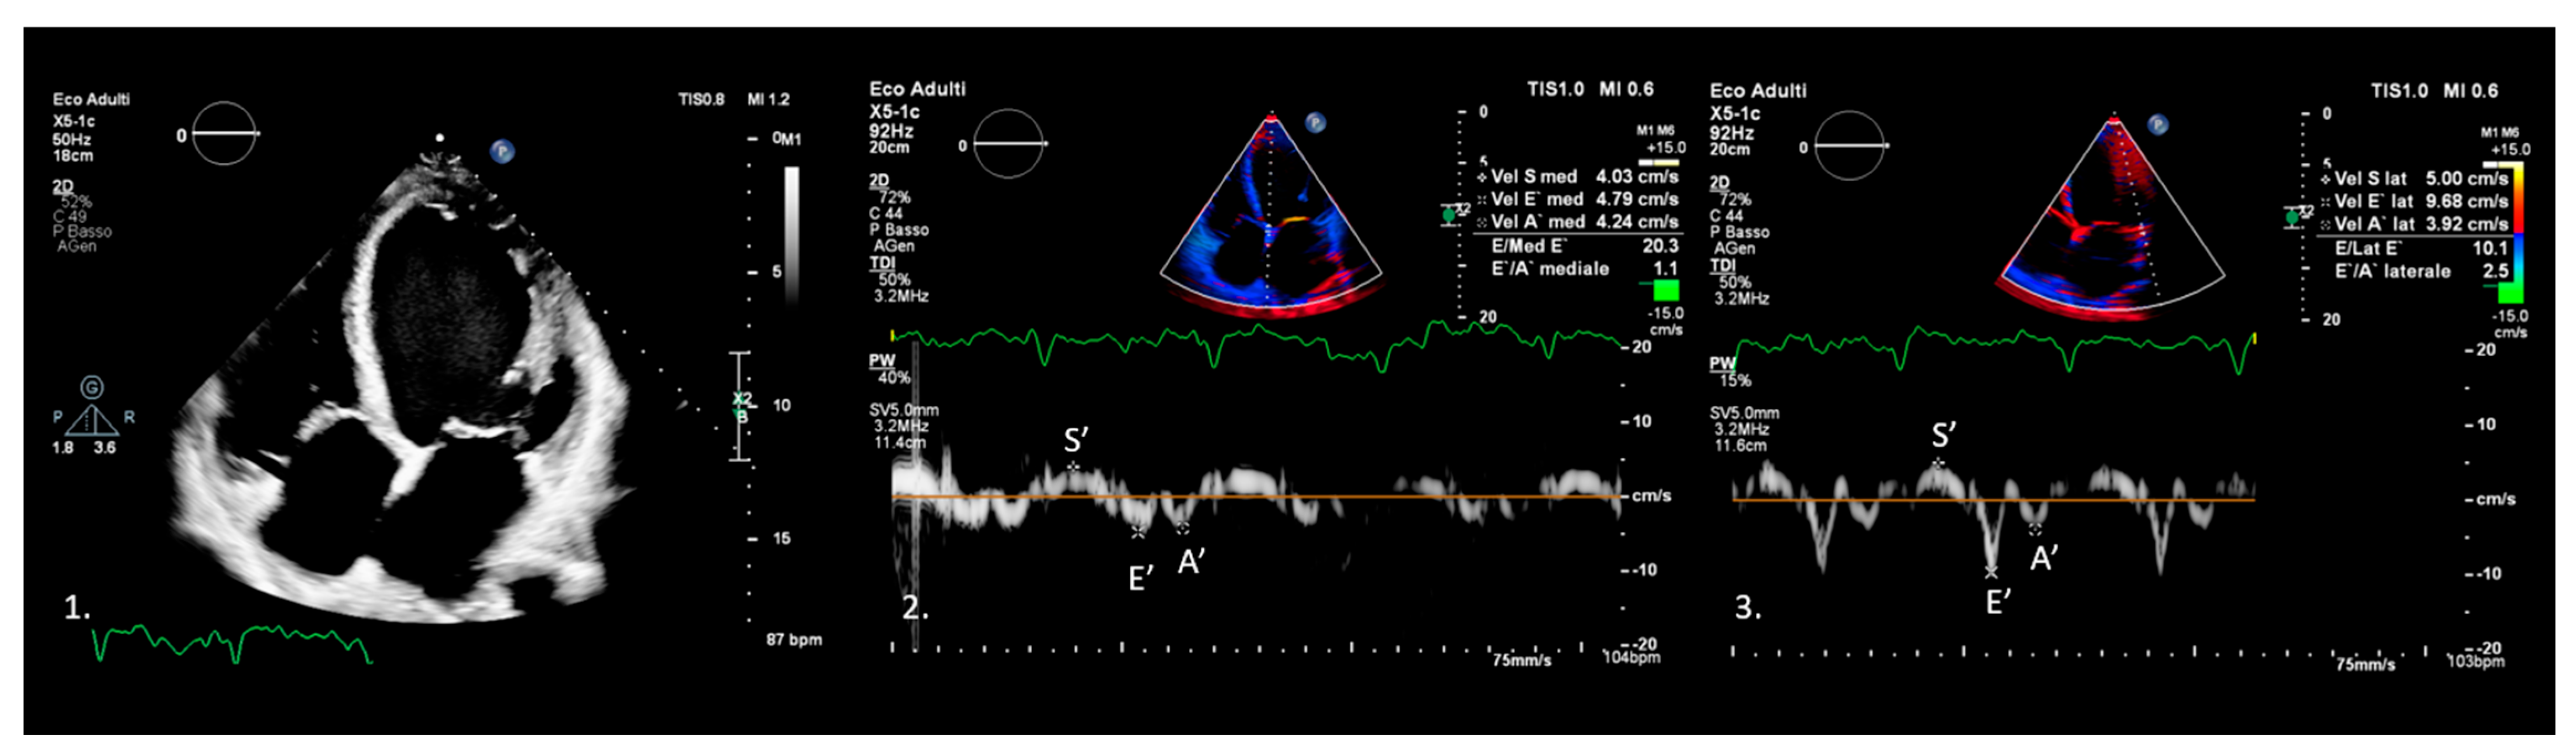

3. Tissue Doppler Imaging Characteristics